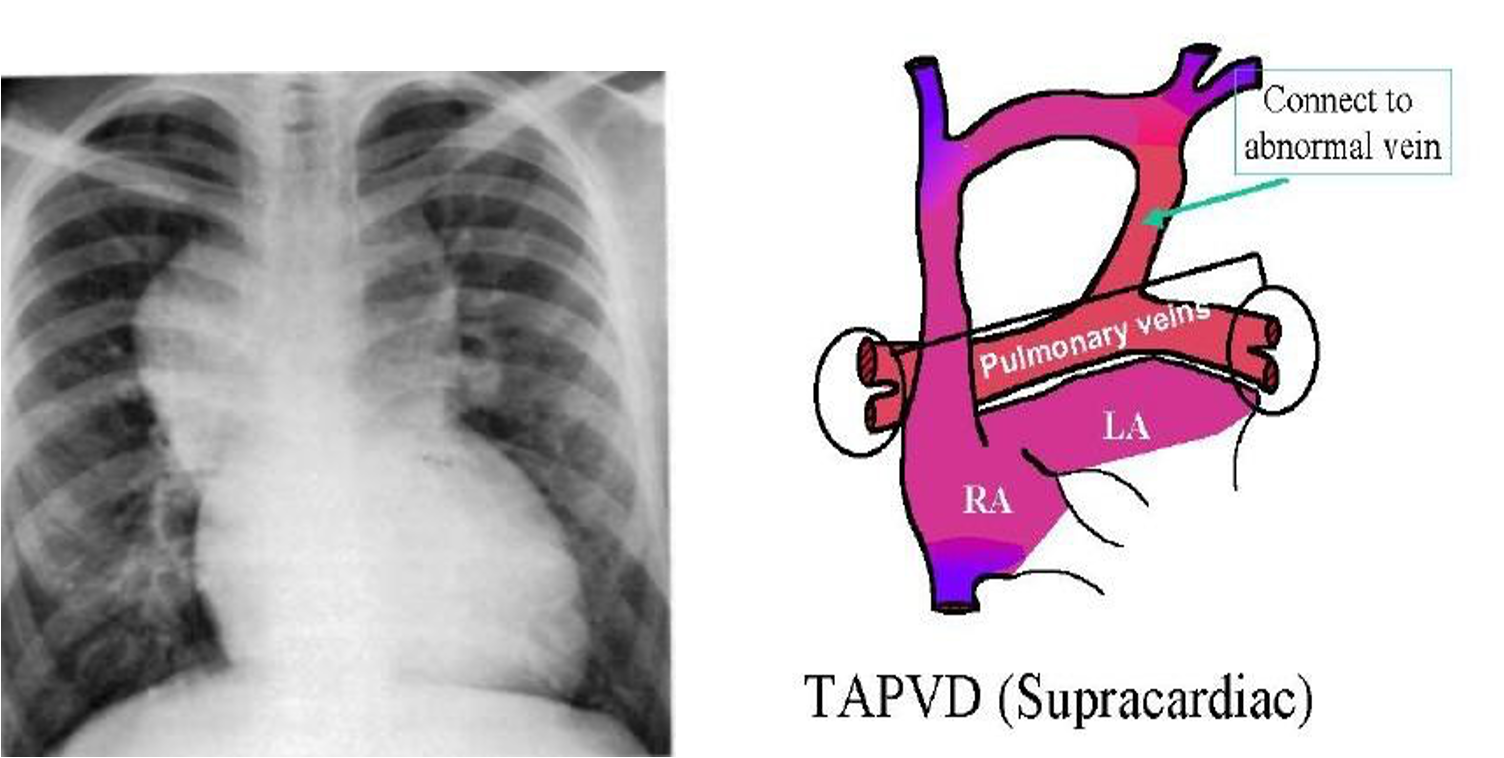

Total Anomalous Pulmonary Venous Drainage

- Blood flow from lungs is drained to RA instead of LA.

Cyanosis & CXR

- CXR may suggest lung disease particularly if the findings are asymmetrical.

- If the changes are diffuse and symmetric, i.e., compatible with pulmonary edema or increased PVM, it is difficult to differentiate between primary lung disease or heart disease causing pulmonary edema, e.g., TAPVD with obstruction.